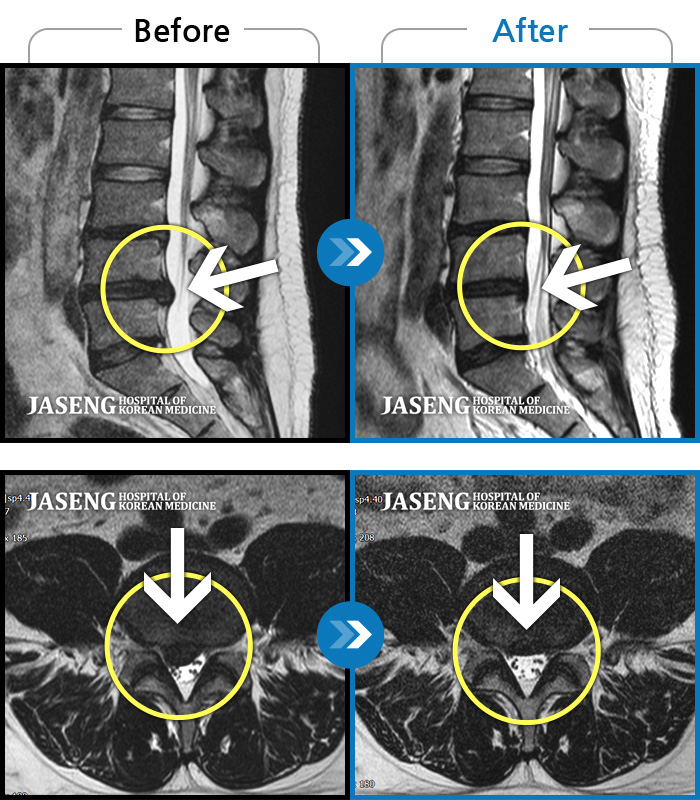

허리디스크

인천 · 강아현 원장

물건을 들다 삐끗한 후 발생한 허리 통증 및 하지 방사통, 하지 감각 저하 및 근력 저하 발생

촬영시기

2025.03.04 ~ 2025.09.10

2025.09.22

조회수 248